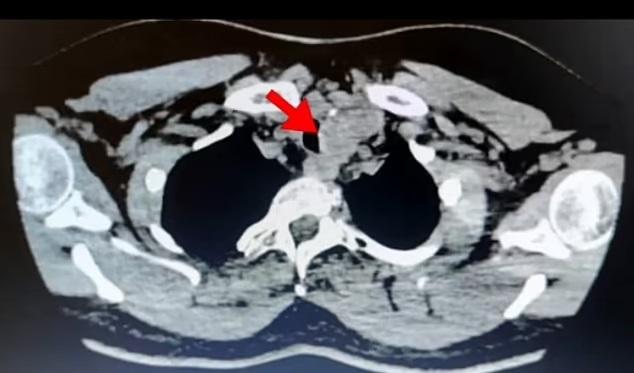

醫生觸摸該名患者頸部並未發現腫脹或腫塊,檢查顯示甲狀腺功能亦正常。連串檢測都找不到原因,最後做電腦掃描和超聲波檢查才發現甲狀腺擴大並局部壓著氣管,以及有很多小瘤,而小瘤有鈣化細點,是癌症明顯徵狀。鑑於腫瘤的體積大,並懷疑癌細胞已擴散到附近周圍,那名女患者需切除整個甲狀腺。在手術後,該病人亦需接受兩輪放射治療。甲狀腺位於頸前方,負責調節身體的新陳代謝,分泌荷爾蒙控制身體使用能量的速度和製造蛋白質等。